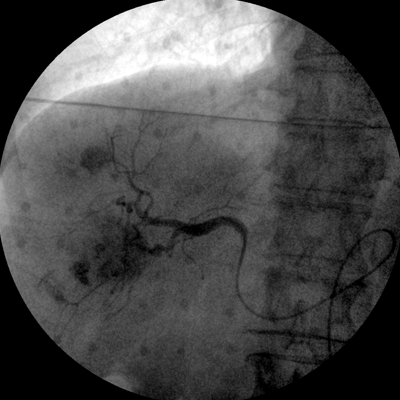

專業(yè)的圖像處理系統(tǒng),為您提供高分辨率、高灰階圖像。